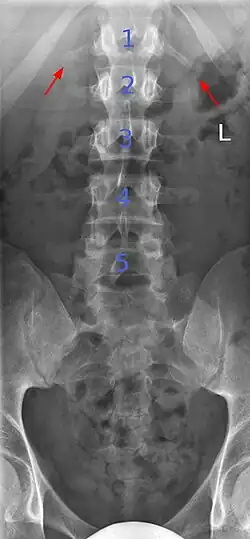

Sacralization of the L5 vertebra is seen at the lower right of the image.

Sacralization of the fifth lumbar vertebra (or sacralization) is a congenital anomaly, in which the transverse process of the last lumbar vertebra (L5) fuses to the sacrum on one side or both, or to ilium, or both. These anomalies are observed in about 3.5 percent of people, and it is usually bilateral but can be unilateral or incomplete (ipsilateral or contralateral rudimentary facets) as well. Although sacralization may be a cause of low back pain, it is asymptomatic in many cases (especially bilateral type). Low back pain in these cases most likely occurs due to biomechanics. In sacralization, the L5-S1 intervertebral disc may be thin and narrow. This abnormality is found by X-ray.